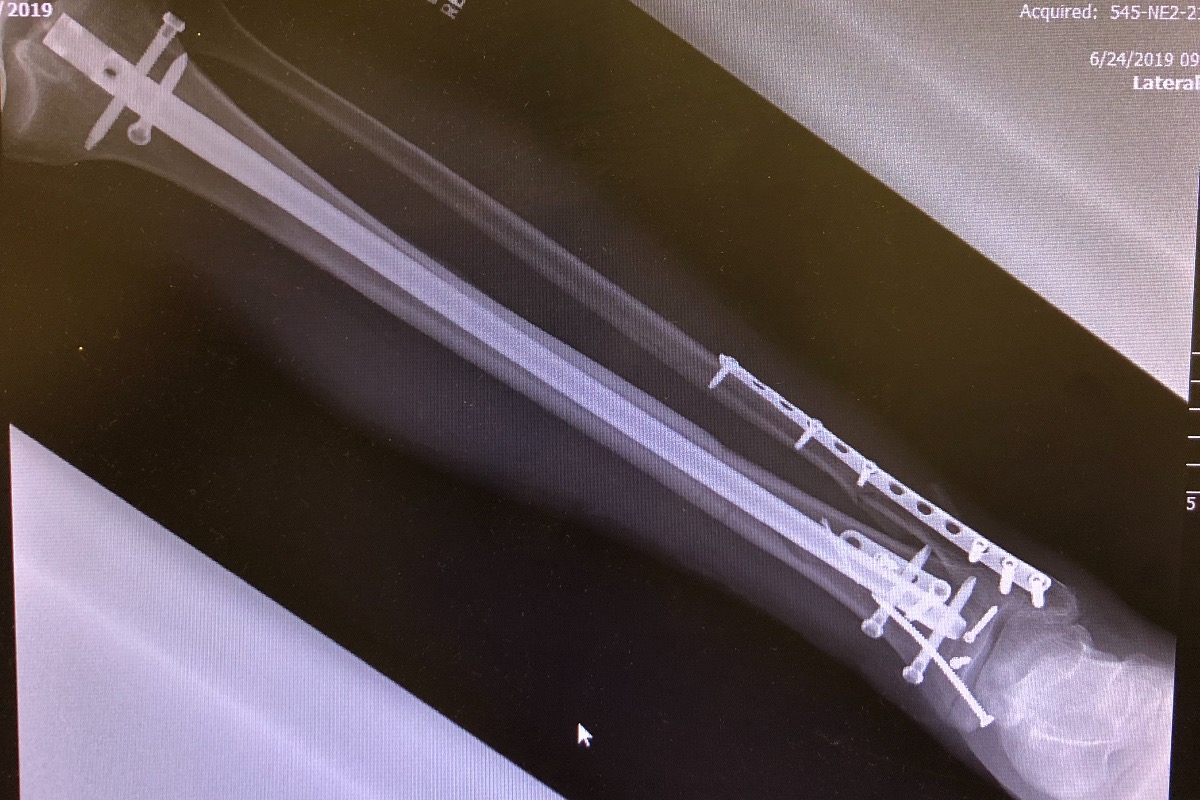

Life seems to make life interesting, after planning my 50th Birthday trip aboard the Cayman Aggressor last year, I was unable to make it. So this year, I rescheduled and had several friends sign up to go with me on this adventure. Unfortunately, I had a very bad, freakish accident recently and broke my lower leg and ankle in FOUR places, yes four places! Per the Orthopedic MD, I can not walk/weight bear on it, let alone dive, for the next 3 months! I do have trip insurance but it did not cover this kind of cancellation, optional option coverage if you understand, so i am trying this Go Fund Me idea at a request of a friend, more importanly, I am also doing this to cover my time out of work and some extra medical expenses that I have incurred. This is the busy time of year for scuba instructors so if we are not working, we are not making money. I have a strong group of friends helping with my immediate financial, medical and yes housing needs, but this is a long term issue. I am side lined for 3 months, will lose out on the 2019 dive season. So any help will be great to help me get through the slow winter season, get back on my feet ( foot) and into the water to do what i love!

Life seems to make life interesting, after planning my 50th Birthday trip aboard the Cayman Aggressor last year, I was unable to make it. So this year, I rescheduled and had several friends sign up to go with me on this adventure. Unfortunately, I had a very bad, freakish accident recently and broke my lower leg and ankle in FOUR places, yes four places! Per the Orthopedic MD, I can not walk/weight bear on it, let alone dive, for the next 3 months! I do have trip insurance but it did not cover this kind of cancellation, optional option coverage if you understand, so i am trying this Go Fund Me idea at a request of a friend, more importanly, I am also doing this to cover my time out of work and some extra medical expenses that I have incurred. This is the busy time of year for scuba instructors so if we are not working, we are not making money. I have a strong group of friends helping with my immediate financial, medical and yes housing needs, but this is a long term issue. I am side lined for 3 months, will lose out on the 2019 dive season. So any help will be great to help me get through the slow winter season, get back on my feet ( foot) and into the water to do what i love!

Life seems to make life interesting, after planning my 50th Birthday trip aboard the Cayman Aggressor last year, I was unable to make it. So this year, I rescheduled and had several friends sign up to go with me on this adventure. Unfortunately, I had a very bad, freakish accident recently and broke my lower leg and ankle in FOUR places, yes four places! Per the Orthopedic MD, I can not walk/weight bear on it, let alone dive, for the next 3 months! I do have trip insurance but it did not cover this kind of cancellation, optional option coverage if you understand, so i am trying this Go Fund Me idea at a request of a friend, more importanly, I am also doing this to cover my time out of work and some extra medical expenses that I have incurred. This is the busy time of year for scuba instructors so if we are not working, we are not making money. I have a strong group of friends helping with my immediate financial, medical and yes housing needs, but this is a long term issue. I am side lined for 3 months, will lose out on the 2019 dive season. So any help will be great to help me get through the slow winter season, get back on my feet ( foot) and into the water to do what i love!